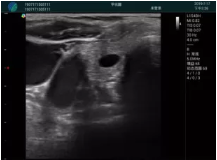

甲狀腺囊性結(jié)節(jié),囊壁鈣化,透聲好

甲狀腺囊性占位

2001年美國健康護(hù)理研究和質(zhì)量監(jiān)督局(AHRQ)批準(zhǔn)了一項(xiàng)關(guān)于提高患者安全性的報(bào)告,建議:在頸內(nèi)靜脈中心置管術(shù)時使用超聲引導(dǎo)。此后超聲引導(dǎo)穿刺被用于幾乎所有的急診穿刺操作,尤其是血管穿刺。

便攜超聲在急診穿刺中的應(yīng)用:

* 提高了穿刺成功率

* 減少了穿刺損傷及并發(fā)癥

* 縮短了操作時間

* 減輕了患者痛苦